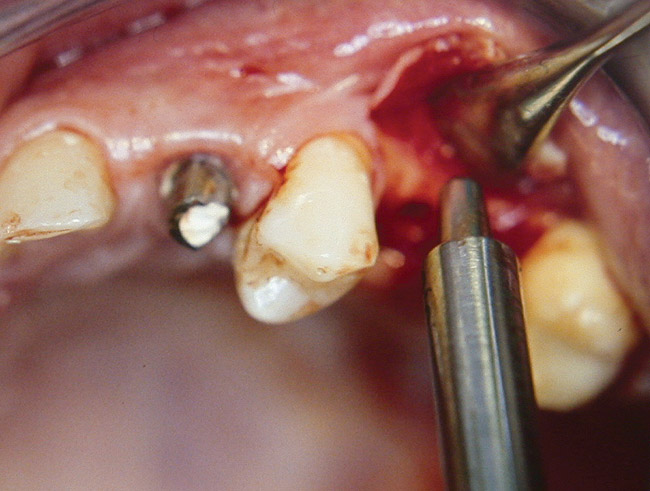

A 53-year-old female was referred for evaluation of a fracture of tooth No. 24. The tooth had been treated endodontically 5 years prior. The radiograph revealed a complete fracture of the tooth involving the crown (Figure 12). Tooth extraction and immediate placement of a an implant that was 10 mm in length and 3.75 in diameter was planned.

At the time of surgery, the tooth was extracted without harvesting any mucosal flap because the implant site was prepared by means of a pilot drill bur (Figure 13) and alternating osteotomes (Figure 14A and Figure 14B). The implant was positioned and showed primary stability. The implant was loaded 2 days after surgery. Then, splinted PFM crowns supported by custom gold abutments were delivered. At 6 months posttreatment, the radiograph revealed no bone resorption and the clinical result was optimal (Figure 15A and Figure 15B).

Figure 13  The drill bur was used to start the implant site preparation.

Figure 13